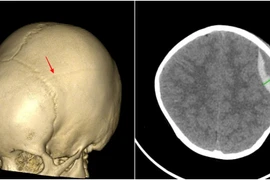

Bé 3 tuổi bị tụ máu não sau ngã, cảnh báo tai nạn sinh hoạt ở trẻ nhỏ

Chấn thương sọ não ở trẻ nhỏ là tai nạn sinh hoạt xảy ra khá phổ biến, nguy cơ để lại di chứng nặng nề, đe dọa tính mạng nếu không được điều trị kịp thời.